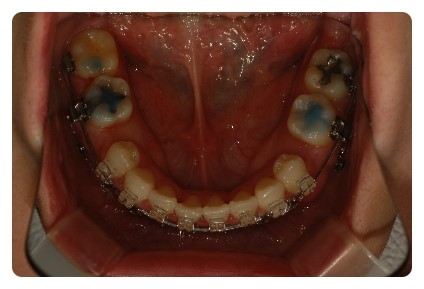

하지만 하악은 발치공간이 아직 마니 남앗어요

유치 발치라 ~~~

뿌리가 짧아서 발치하고나면 빨리 아물고 잇몸뼈도 빨리 단단해져 버려요

그래서 진행이 더딜수밖에 없어요